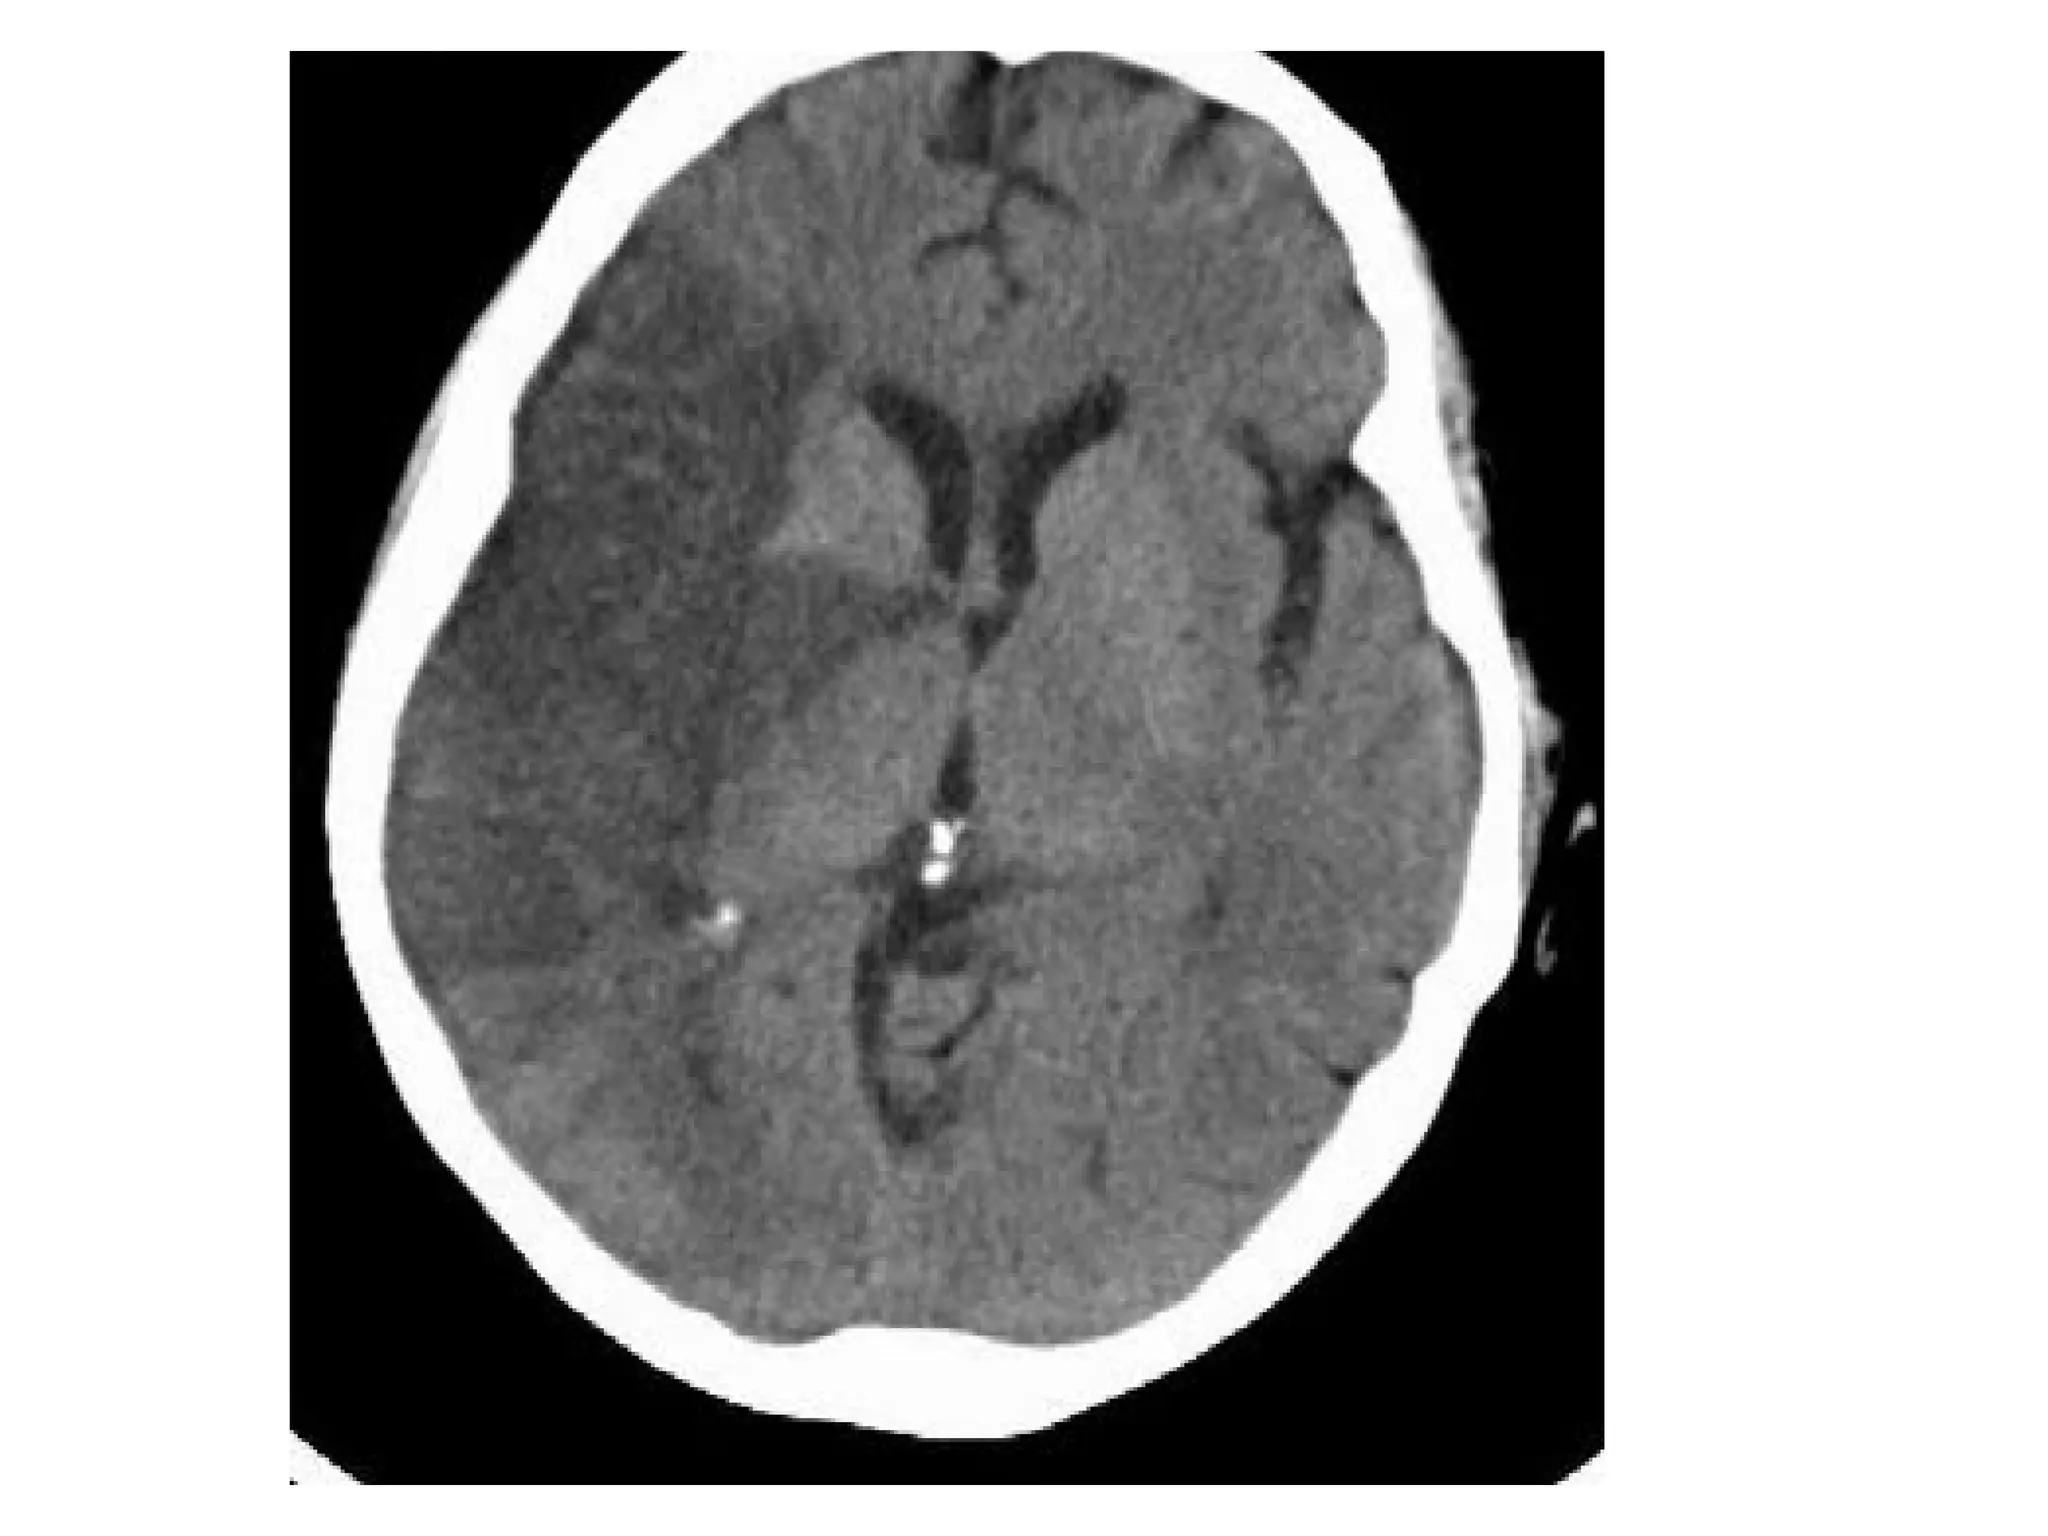

Patient with deep cerebral vein thrombosis , notice the bilateral infarctions in

the basal ganglia